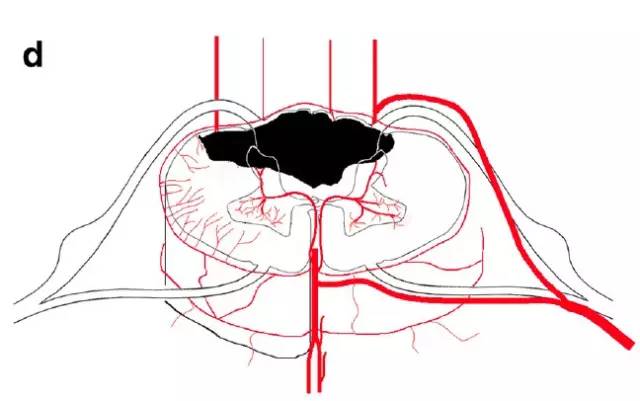

图d,脊髓后动脉/脊髓后外侧动脉分布区梗死

图f,脊髓前角内外系统之间的分水岭区梗死(蛇眼征)